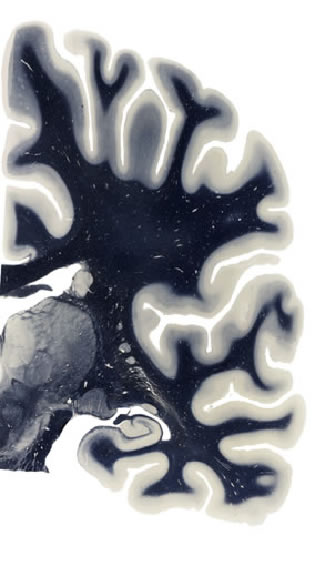

Hi-Resolution Sections · Cells (Nissl Staining) · Virtual Microscopy

Frontal sections (Nissl) from the Atlas Brain:

Macroscopy

Schematic

Slice ID:

r3-0405

Plate NR:

42

Position:

26,5 mm